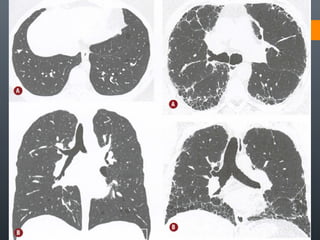

O documento discute vários conceitos radiológicos incluindo consolidação, atelectasia, nódulos, pseudocavidades e padrões intersticiais, fornecendo definições, sinais e diagnósticos diferenciais para cada tópico. Ele também discute a redução da atenuação pulmonar e fornece um link para mais informações.